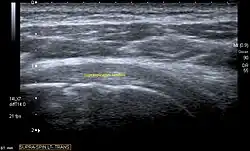

Ultrasound

There are several advantages of ultrasound. It is relatively cheap, does not emit any radiation, is accessible, is capable of visualizing tissue function in real time, and allows the performance of provocative maneuvers in order to replicate the patient’s pain.[28] Those benefits have helped ultrasound become a common initial choice for assessing tendons and soft tissues. Limitations include, for example, the high degree of operator dependence and the inability to define pathologies in bones. One also has to have an extensive anatomical knowledge of the examined region and keep an open mind to normal variations and artifacts created during the scan.[29]

Although musculoskeletal ultrasound training, like medical training in general, is a lifelong process, Kissin et al. suggests that rheumatologists who taught themselves how to manipulate ultrasound can use it just as well as international musculo-skeletal ultrasound experts to diagnose common rheumatic conditions.[30]

After the introduction of high-frequency transducers in the mid-1980s, ultrasound has become a conventional tool for taking accurate and precise images of the shoulder to support diagnosis.[31][32][33][34][35]

Adequate for the examination are high-resolution, high-frequency transducers with a transmission frequency of 5, 7.5, and 10 MHz. To improve the focus on structures close to the skin an additional "water start-up length" is advisable. During the examination the patient is asked to be seated, the affected arm is then adducted and the elbow is bent to 90 degrees. Slow and cautious passive lateral and/or medial rotations have the effect of being able to visualize different sections of the shoulder. In order to also demonstrate those parts which are hidden under the acromion in the neutral position, a maximum medial rotation with hyperextension behind the back is required.[36]

To avoid the different tendon echogenicities caused by different instrument settings, Middleton compared the tendon’s echogenicity with that of the deltoid muscle, which is still lege artis.[37][38]

Usually the echogenicity compared to the deltoid muscle is homogeneous intensified without dorsal echo extinction. Variability with reduced or intensified[39] echo has also been found in healthy tendons. Bilateral comparison is very helpful when distinguishing and setting boundaries between physiological variants and a possible pathological finding. Degenerative changes at the rotator cuff often are found on both sides of the body.[40] Consequently, unilateral differences rather point to a pathological source and bilateral changes rather to a physiological variation.[38]

In addition, a dynamic examination can help to differentiate between an ultrasound artifact and a real pathology.[41]

To accurately evaluate the echogenicity of an ultrasound, one has to take into account the physical laws of reflection, absorption and dispersion. It is at all times important to acknowledge that the structures in the joint of the shoulder are not aligned in the transversal, coronal or sagittal plane, and that therefore during imaging of the shoulder the transducer head has to be held perpendicularly or parallel to the structures of interest. Otherwise the appearing echogenicity may not be evaluated.[42]

Longitudinal ultra sonography of the supraspinatus tendon

Transversal ultra sonography of the supraspinatus tendon